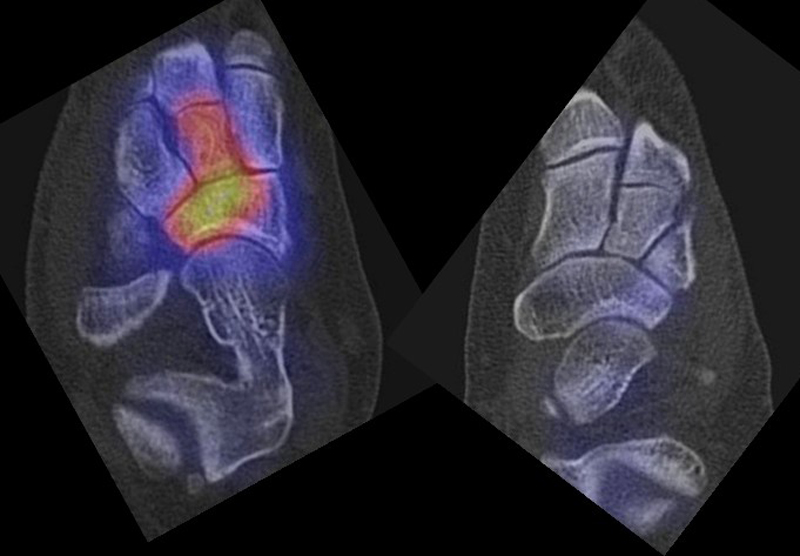

SPECT/CT bei Coalitionen

Coalitionen können auf Röntgenbildern wegen überlappender Strukturen häufig nicht sicher diagnostiziert werden, so dass MRT und/oder CT erforderlich sind, um eine Coalitio eindeutig nachzuweisen. Der Vorteil der SPECT/CT liegt darin, dass neben der submilimeter-genauen Darstellung der Anatomie, womit die charakterischten Röntgenzeichen einer Coalitio erkannt werden, auch die Stressreaktion bzw. die Scherkräfte, die auf die Syndesmose oder Synchondrose wirken, sichtbar gemacht werden können. Dabei hat die SPECT/CT eine deutlich höhere Treffsicherheit als die MRT zur exakten Lokalisation der Stressreaktion 44.

Abbildung 4.1.zeigt das Beispiel einer Patientin mit einer Stressreaktion zwischen Processus anterior calcanei und Os naviculare, welche einer fibrösen symptomatischen Coalitio entspricht, die primär in der Bildgebung (Röntgen, MRT) nicht erkannt wurde. Bei Knick-Senk-Fuß erfolgte zunächst eine Talo-Naviculare Arthrodese. Postoperativ nahmen die Schmerzen zu. Anstelle eines SPECT/CT erhielt die Patientin zwei Serien einer Röntgen-Reiz-Bestrahlung. Die Patientin stellte sich in einer auf Fußerkrankungen spezialisierten Klinik vor, die die Patientin zur weiteren Abklärung zu uns überwies. Erst die Abklärung mittels SPECT/CT zeigte die eine fibröse Coalitio zwischen Processus anterior calcanei und Os naviculare bei vollständig reizlos durchbauter Talo-Navicularer Arthodese. Es wurde daraufhin eine erfolgreiche konservative Therapie u. a. mittels gezielten Injektionen und Stosswellen eingeleitet.

Die Abbildungen 4.2.a bis d zeigen den typischen Aspekt einer talacalcanearen Coalitio. Es besteht nur eine linksseitige, symptomatische Coalitio talocalcaneare (4.2.a und c); das 35 Tage zuvor angefertigte MRT zeigt keine auffälligen Signalveränderungen (4.2.b und d).

Abbildung 4.3. zeigt die Ursache für rechtsseitige Sprunggelenksbeschwerden bei einem Patienten mit talocalcanearen Coalitionen: nur die osteochondrale Läsion an der distalen rechten Tibia ist die Ursache des Schmerzes. Die bilateralen talocalcanearen Coalitionen sind asymptomatisch.